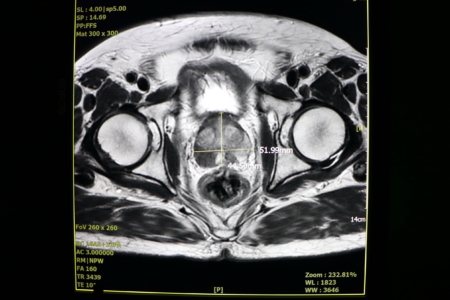

4. 超音波:可以正確測量攝護腺大小與膀胱殘留尿量。